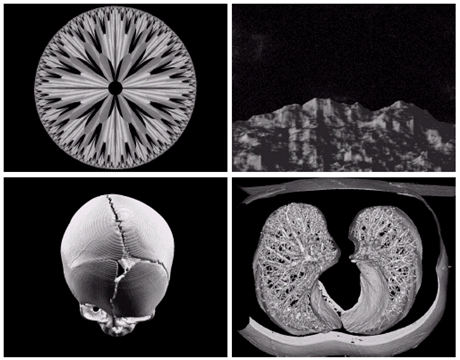

- 전자현미경: SEM(scanning electron microscope)

- 전자빔을 쏘아 각 위치에서 빔과 샘플과의 상호작용을 기록

텅스텐필라멘트의 250x SEM영상, 손상된 IC의 250x SEM영상